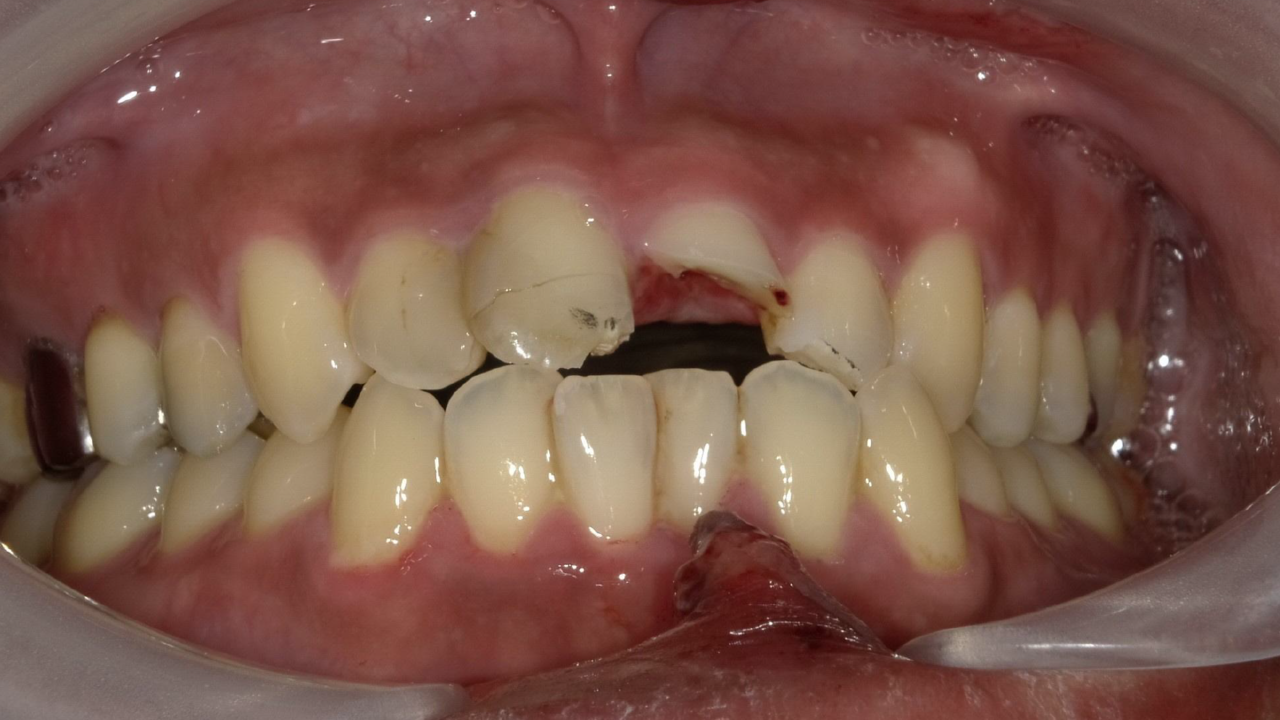

T・K様 男性 30代

Before

After

キックボードで転倒し前歯を受傷されました。上の前歯は2本とも歯冠が割れていて歯の神経が見えている状態でした。抜歯はせず、歯を出来る限り残した治療を予定しました。神経の治療後、審美的にジルコニアクラウンを希望されました。治療後は痛みもなく、見た目も綺麗で抜歯もせず治療ができたと大変満足されていました。

治療期間・回数:2か月、6回

治療の価格:ジルコニアクラウン ¥137,500(1歯)

治療のリスクや副作用:保険適応外。特にジルコニアは硬度が高いため、素材の厚みを確保するために歯を多く削ることがある点がデメリットです。